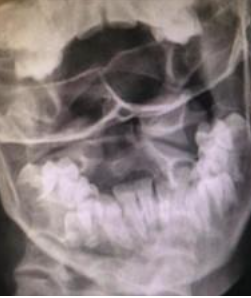

Qual é o exame radiográfico chave para a Síndrome de Grisel?

RX Transoral, que avalia a presença de assimetria no espaço entre o odontóide e as massas laterais de C1.

O que indica o “Wink Sign” em radiografias na Síndrome de Grisel?

Desaparecimento da articulação entre C1 e C2 no RX AP transoral.

Quais são os sinais radiográficos importantes na Síndrome de Grisel?

Assimetria no espaço entre o odontóide e as massas laterais de C1 e o Wink Sign.